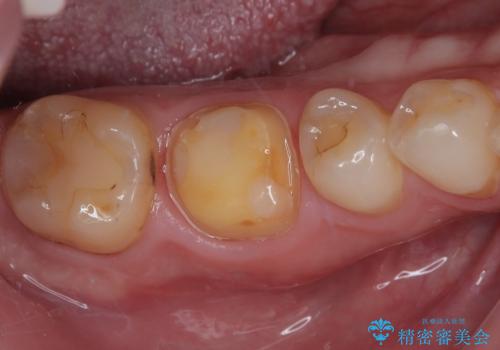

- セラミックの詰め物が欠けたのでやり替えたいとのことで来院された患者様です。

右下の6番目の歯は初診時から詰め物が大きかったため、被せものでの治療を提案していましたが、患者様の強いご希望でセラミックの詰め物(セラミックインレー)での治療をされていました。今回メインテナンス時に来院されたときに被せもの(オールセラミッククラウン)での治療を再度提案させていただき、患者様にも納得をしていただいたうえで、オールセラミッククラウンによる治療を行いました。

拡大鏡視野下で、セラミックの詰め物(セラミックインレー)、虫歯の除去を行い、オールセラミッククラウンに適した形に整えました。